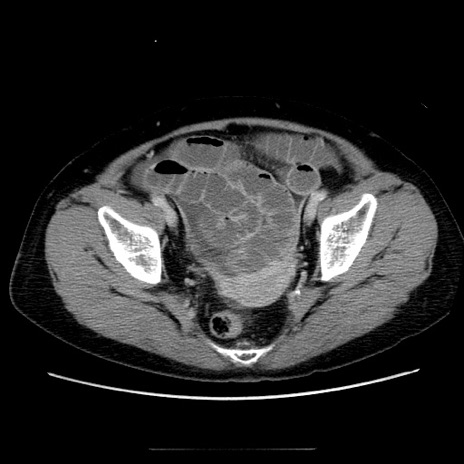

症例5(横断像)

【症例】70歳代女性

【主訴】お腹が張る

【現病歴】1週間くらい前から腹部膨満の自覚あり。昨日夜から増悪したため、本日救急外来受診。

【身体所見】意識清明、BT 36.5℃、BP 165/106mmHg、HR 80bpm、SpO2 98%、腹部:膨満、軟、自発痛・圧痛なし、触診にて不快感あり、腸蠕動音:減弱

【データ】WBC 12600、CRP 1.04